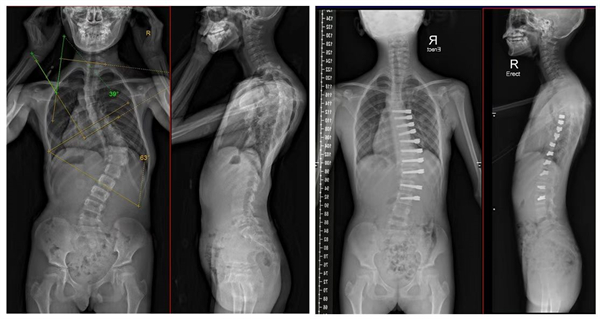

左為術前全脊柱正側位X線片,主彎Cobb角63°。右為術後全脊柱正側位X線片,側彎角度明顯減小,且隨着生長發育,側彎會進一步改善。